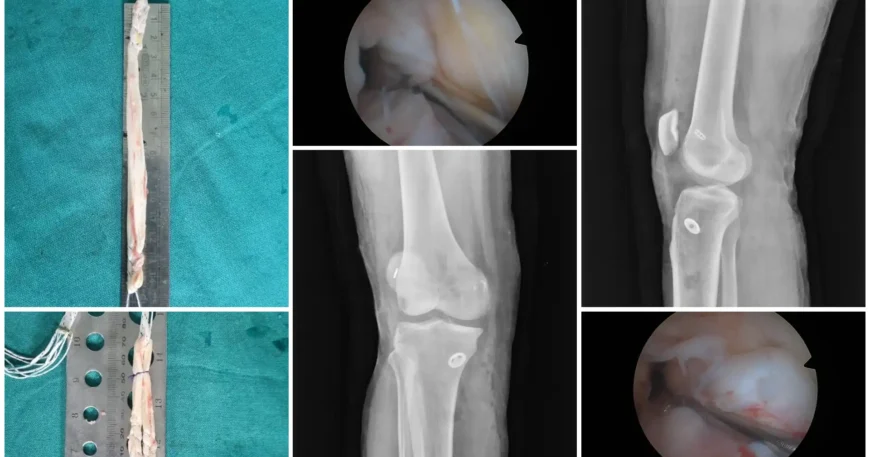

Arthroscopic ACL Reconstruction with Hamstring Graft

Mr. Akshay underwent arthroscopic ACL reconstruction using a hamstring tendon graft, a minimally invasive technique that offers excellent strength and long-term outcomes.

The torn ACL was replaced with a hamstring graft and securely fixed using advanced surgical devices under arthroscopic guidance.